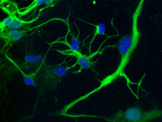

Previously, we established a stem cell repository, comprised of human pluripotent stem cells as well as patient derived iPS cells. We were the first to publish the use of human pluripotent stem cells (hPSC) as a model for alcohol toxicity in early human development. We found that exposure of undifferentiated hPSCs to low yet clinically relevant amounts of ethanol (20mM) leads to enhanced cell death, proliferation and changes in neuronal and glial cell differentiation patterns.

Through whole genome expression analysis, we discovered changes in the expression of over 500 genes a result of ethanol exposure, however 75 had direct contribution in the area of human development, neuronal and glial cell assembly, proliferation, differentiation, and cell death. Additionally, we have identified changes in the expression of GABA, NMDA, and CHRN receptors. These receptors are associated with drug Addiction and substance abuse, and have been shown to have different expression patterns in genetically diverse populations. We will expand our alcohol stem cell repository to include alcohol addicted/abusing patient derived-iPS cells with identified mutation and conduct validation comparisons to our existing alcohol treated hPSCs. This expansion will include iPS cells derived from a genetically diverse population that represents the drinking community in the United States, as alcohol metabolism and biological differences have been reported to differ based on genetic diversity. These cell will possess all of the disease hallmarks including genetic mutation, and the following are the expected benefits: